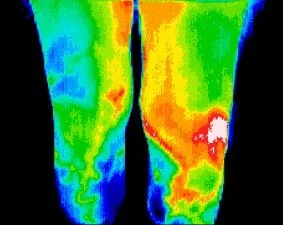

Sports Injury/Region of Interest Thermography Scan

This imaging series correlates with the needs of the patient. Ranging from a Full Body scan to a Region/Area of Interest, these scans are a used as a tool in the differential diagnosis of neuromusculoskeletal injuries, back pain, joint pain, stress fractures and their prognosis for return to participation and/or competition.

Since DITI is a non-invasive and risk free scan, it is a very practical tool to be used in a sports medicine setting and aid the assessment of injury and making clinical decisions.

DITI not only helps confirm a diagnosis, but can be used as a gauge to clinically assess progress and rehabilitation treatment response. DITI is useful for, but not limited to, aiding the diagnosis and evolution of epicondylitis, patellofemoral syndromes, ankle injuries, shin splints, stress fractures, myofascial pain syndromes, spinal pain syndromes, shoulder injuries, foot pain syndromes, and vascular disorders.